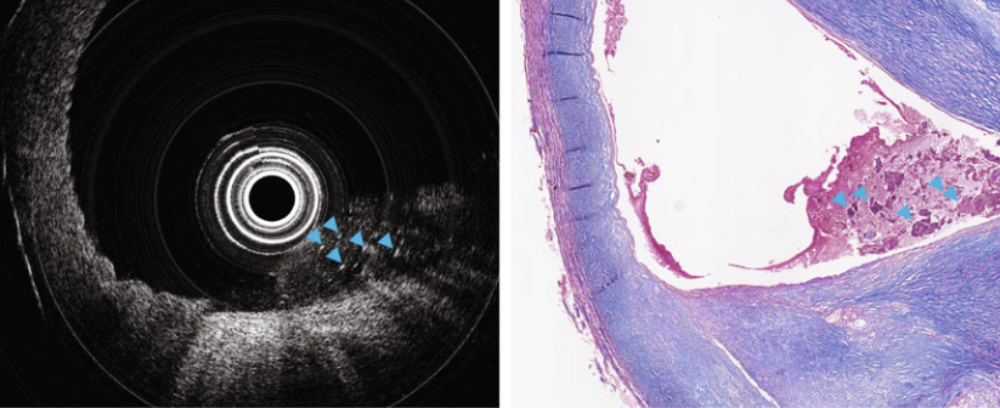

3D-gedrucktes Mini-Endoskop macht Bilder im Inneren von Adern